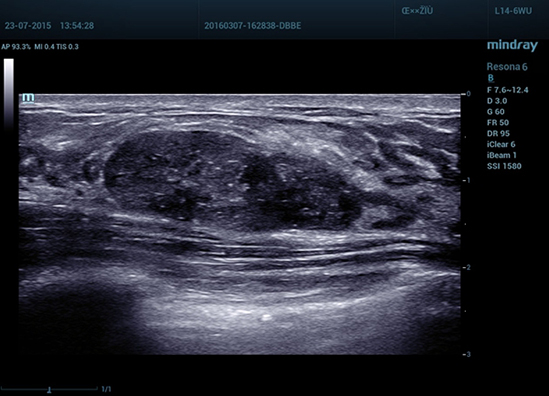

–Ь–µ—В–Њ–і —Н–ї–∞—Б—В–Њ–≥—А–∞—Д–Є–Є Natural Touch

Natural Touch –Њ–±–µ—Б–њ–µ—З–Є—В—М –љ–µ–њ—А–µ–≤–Ј–Њ–є–і–µ–љ–љ—Г—О —З—Г–≤—Б—В–≤–Є—В–µ–ї—М–љ–Њ—Б—В—М –Є –Њ—В–ї–Є—З–љ—Г—О –≤–Њ—Б–њ—А–Њ–Є–Ј–≤–Њ–і–Є–Љ–Њ—Б—В—М —А–µ–Ј—Г–ї—М—В–∞—В–Њ–≤ –≤–љ–µ –Ј–∞–≤–Є—Б–Є–Љ–Њ—Б—В–Є –Њ—В –љ–∞–≤—Л–Ї–Њ–≤ –Њ–њ–µ—А–∞—В–Њ—А–∞, –њ–Њ–≤—Л—И–∞–µ—В –Ї–ї–Є–љ–Є—З–µ—Б–Ї—Г—О –Ј–љ–∞—З–Є–Љ–Њ—Б—В—М –Љ–µ—В–Њ–і–∞ –Є —А–∞—Б—И–Є—А—П–µ—В –≤–Њ–Ј–Љ–Њ–ґ–љ–Њ—Б—В–Є –µ–≥–Њ –њ—А–Є–Љ–µ–љ–µ–љ–Є—П. –£–љ–Є–Ї–∞–ї—М–љ—Л–є –∞–љ–∞–ї–Є–Ј –Ј–Њ–љ—Л –Њ–±–Њ–і–Ї–∞ вАФ –Є—Б–Ї–ї—О—З–Є—В–µ–ї—М–љ–Њ –њ–Њ–ї–µ–Ј–љ—Л–є –Є–љ—Б—В—А—Г–Љ–µ–љ—В –і–ї—П –Њ—Ж–µ–љ–Ї–Є –і–Њ–±—А–Њ–Ї–∞—З–µ—Б—В–≤–µ–љ–љ—Л—Е –Є –Ј–ї–Њ–Ї–∞—З–µ—Б—В–≤–µ–љ–љ—Л—Е –Њ–±—А–∞–Ј–Њ–≤–∞–љ–Є–євАФ –њ—А–µ–і–Њ—Б—В–∞–≤–ї—П–µ—В –і–∞–љ–љ—Л–µ –Њ –Ї–Њ—Н—Д—Д–Є—Ж–Є–µ–љ—В–µ –і–µ—Д–Њ—А–Љ–∞—Ж–Є–Є –Љ–µ–ґ–і—Г –Њ–Ї—А—Г–ґ–∞—О—Й–µ–є —В–Ї–∞–љ—М—О –Є –њ–Њ—А–∞–ґ–µ–љ–љ—Л–Љ —Г—З–∞—Б—В–Ї–Њ–Љ, —З—В–Њ –њ–Њ–Ј–≤–Њ–ї—П–µ—В –Њ—Ж–µ–љ–Є—В—М —Б—В–µ–њ–µ–љ—М –Є–љ—Д–Є–ї—М—В—А–∞—Ж–Є–Є —А–∞–Ї–Њ–≤—Л—Е –Ї–ї–µ—В–Њ–Ї –≤ –Њ–Ї—А—Г–ґ–∞—О—Й–Є–µ –Њ–њ—Г—Е–Њ–ї—М —В–Ї–∞–љ–Є.